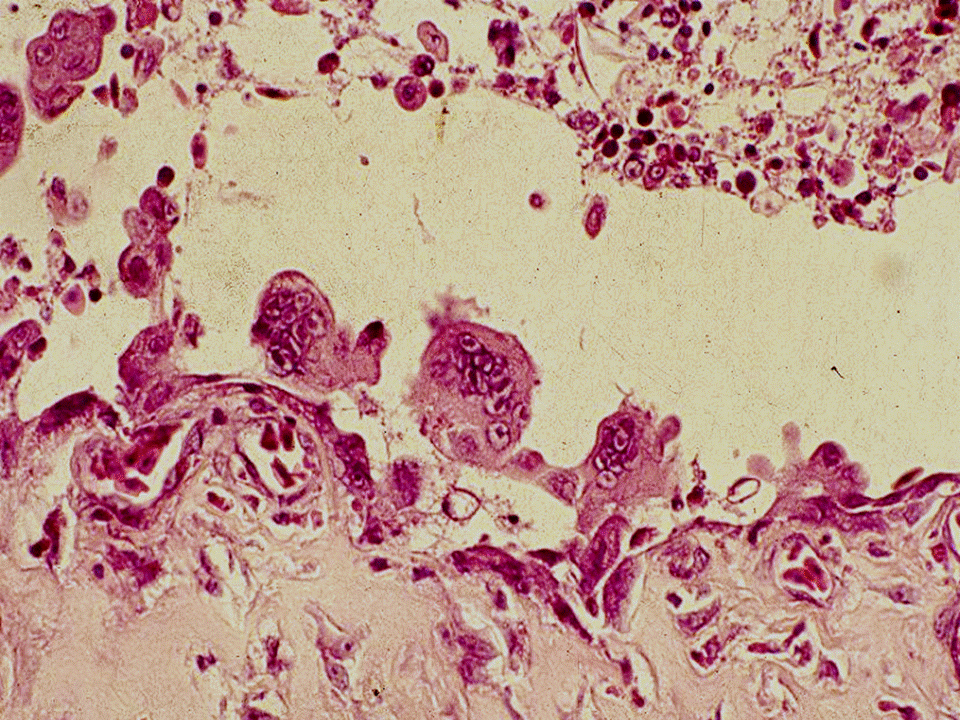

疾病中文名稱:傳染性喉頭氣管炎

疾病英文名稱:Infectious laryngotracheitis

作者:蔡信雄教授